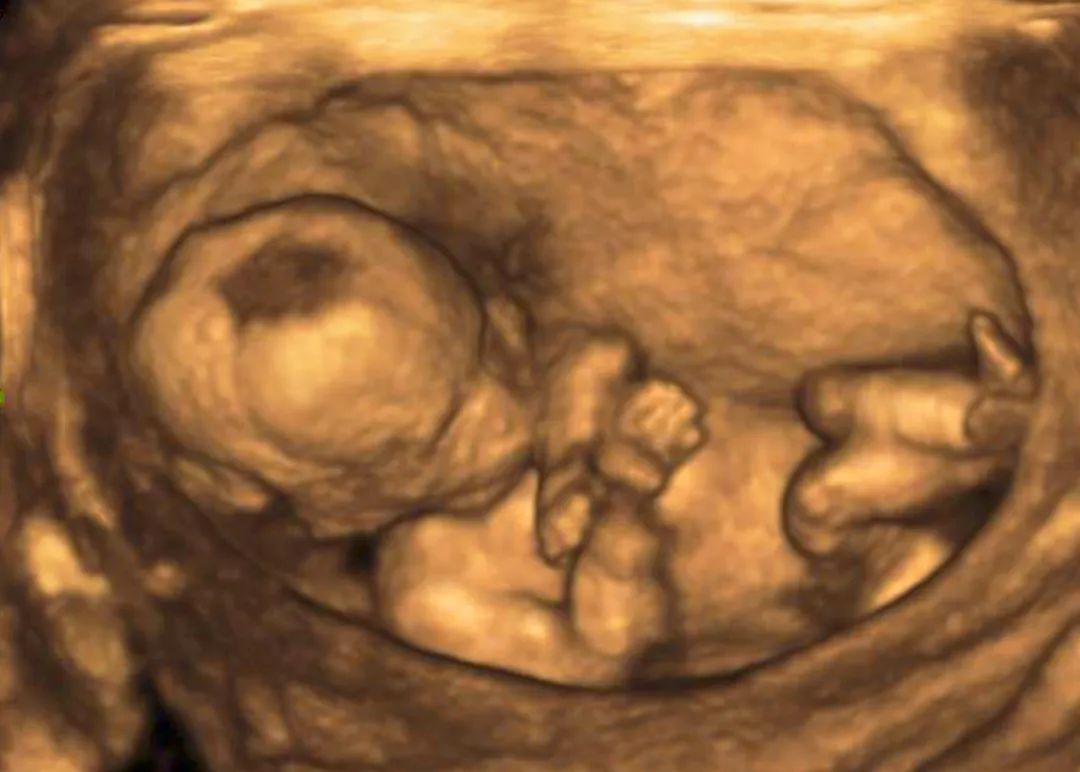

在孕20周-24周的宝妈,千万别忘了做9大畸形筛查(四维彩超)哦。